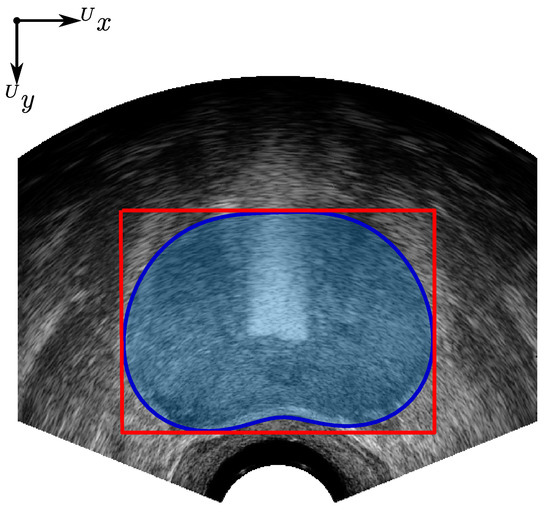

where and . The height and width of the prostate contour, measured in mm in the ultrasound image frame and axes, are found from the height and width of a bounding box containing the prostate contour; see Figure 12. The average width and height of the algorithmic and clinician segmented prostate contours, with respect to image depth, are presented in Figure 13. For measuring the area and volume of the prostate, a polygon is fit to points on the prostate contour model or clinician-segmented contour for each slice i, as shown in Figure 12, with the resulting polygon areas, and for the algorithmic and clinician contours respectively, calculated in metric units (mm2). To calculate the volume of the prostate for the algorithm and clinician contours , the area of each slice was multiplied by the 5 mm TRUS image slice stepping distance and summed for all of the slices in the image set, such that

Figure 12.

Bounding box, indicated in red, and shaded-blue polygon contour area used for prostate contour height, width, and volume measurements.